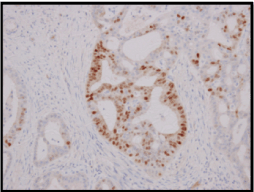

A wide local excision of the tumour was done (Figure3), which was reported as a 5x2x1.5cm irregular mass composed of cells arranged in fused glandular formation and cribriform pattern, consistent with metastatic adenocarcinoma (Slide 4). The tumour cells are positive for ER (Slide 5), PR (Slide 6), CK7, E-cadherin and mammaglobin. The immunoprofile is consistent with a metastatic breast carcinoma. The underlying skeletal muscle was uninvolved.

Slide 5. Section from metastatic tumour shows Estrogen Receptor positivity.

Slide 6. Section from metastatic tumour shows Progesterone Receptor positivity.